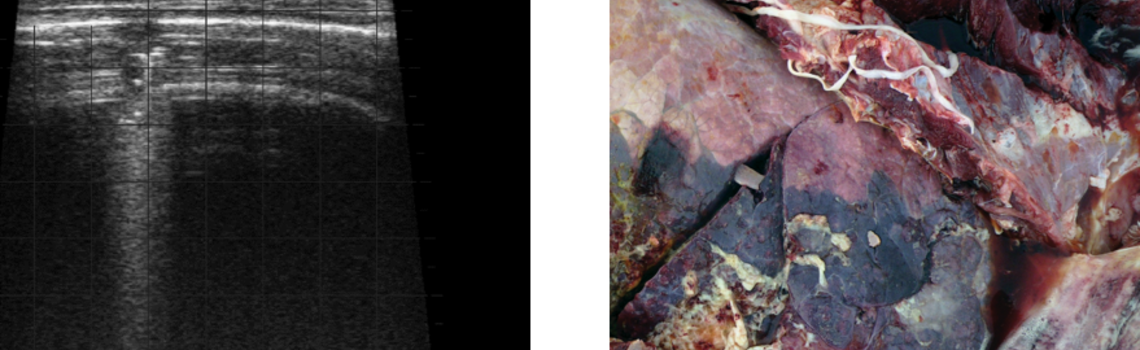

The below images show the difference between healthy lung and a lung that has been damaged by BRD. As calves have a smaller lung capacity compared to other animals, further decreased lung capacity has a significant lifetime impact in terms of future growth and productivity.8

A: Healthy lung B: Severe and extensive lesion preventing air flow through the entire lung lobe